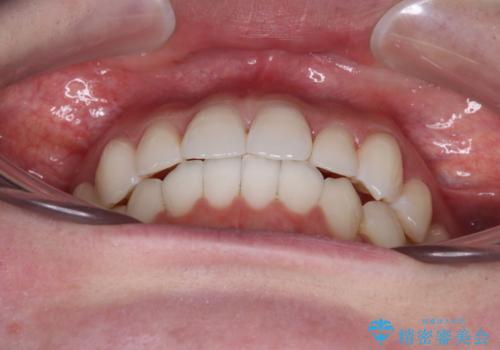

ワーキングホリデー前にきれいな歯列に

- 2、3年後にワーキングホリデーで海外に行くため、その前に歯列やむし歯をきれいにしたいとのことで来院された患者様です。

抜歯の必要な右上の奥歯は事前に抜歯をし、インビザラインにて上下歯列を整えることとしました。

矯正治療後半に奥歯の補綴治療が必要な歯にはオールセラミッククラウンを装着し、インビザラインで最終的に仕上げることとしました。

海外に行く前に口腔内環境を整えることができ、患者様には大変満足していただきました。